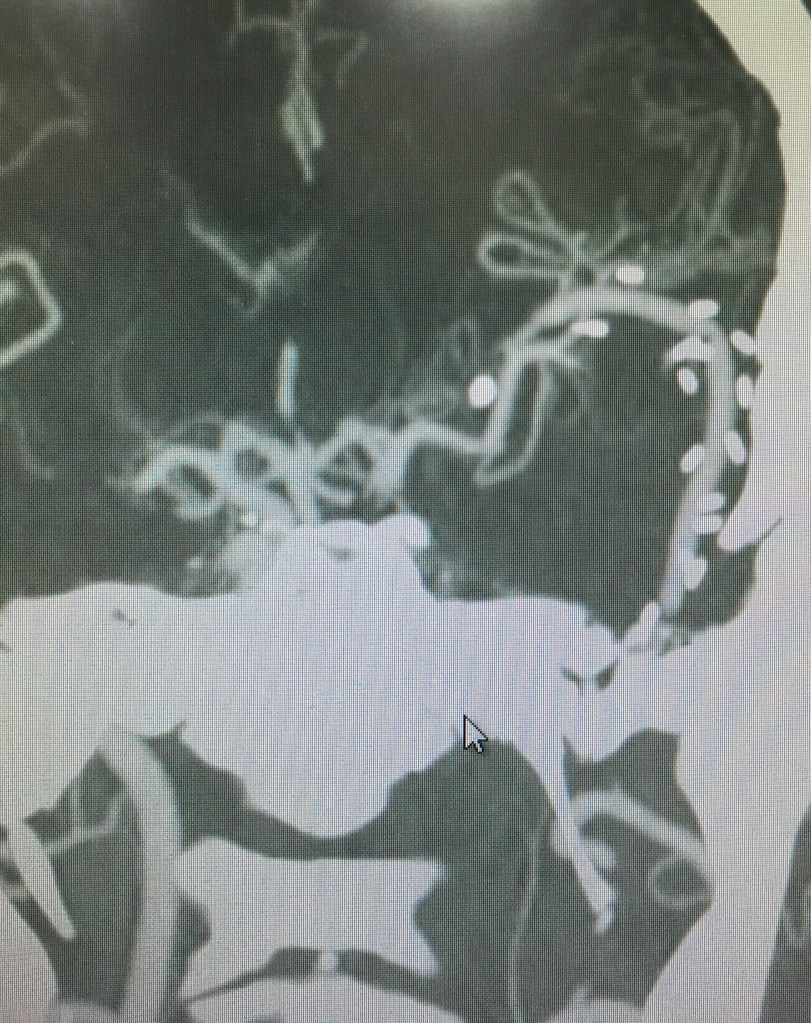

- เส้นเลือดสมองโป่งพอง(Cerebral Aneurysm)

- เส้นเลือดผิดปกติในสมอง(AVM, Cavernoma)